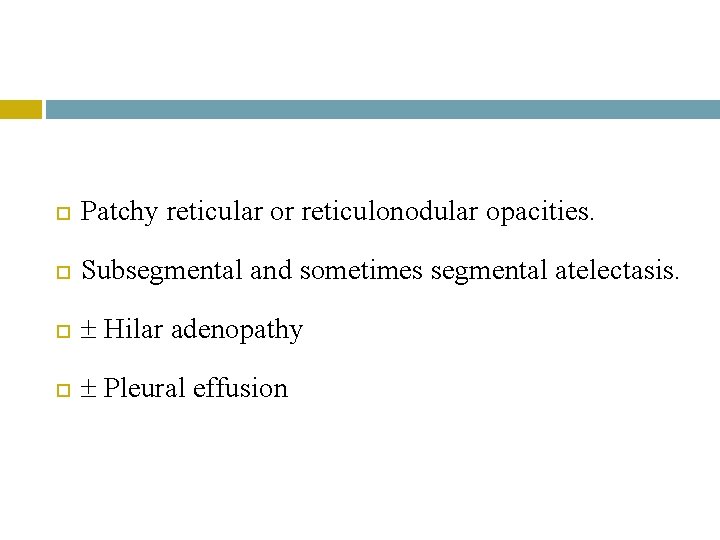

Radiology

Patchy reticular or reticulonodular opacities. Subsegmental and sometimes segmental atelectasis. Hilar adenopathy Pleural effusion